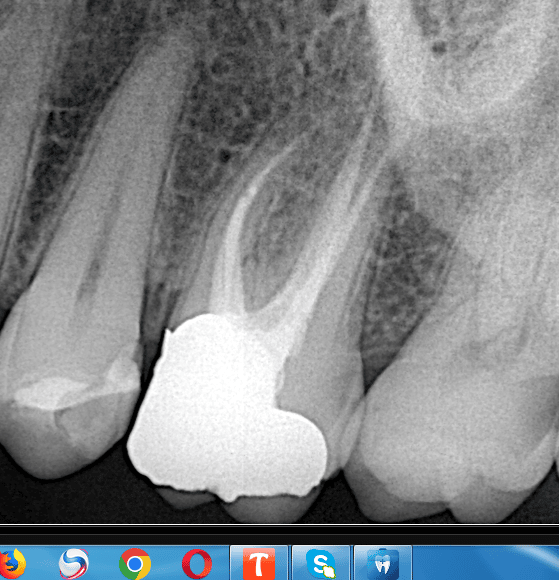

Preoperative x ray

Final x ray , look to the fitness of the lithium disilicate on the biobase